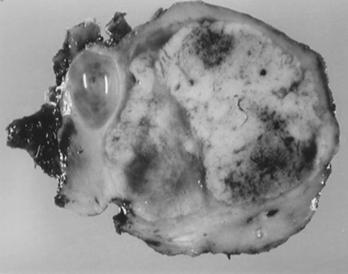

Figura 9.5. Boala von Hippel Lindau- numeroase formatini tumorele solide si chistice. (aspect macroscopic si CT) adaptat dupa Bachir Taouli, Mehdi Ghouadni, Jean-Michel Corras, Pascal Hammel, Anne Couvelard, Stphane Richard and Valrie Vilgrain: Spectrum of Abdominal Imaging Findings in von Hippel-Lindau Disease, American Journal of Roentgenology

Exista forme de trecere progresiva de la chisturi simple unistratificate pana la neoplasm renal cu celule clare trecand prin toate formele intermediare atipice. Chisturile simple se dezvolta mai ales din tubii contorti distali, in timp ce neoplasmele si chisturile atipice provin din tubii contorti proximali. Majoritatea leziunilor chistice pure raman stabile, in timp ce chistele atipice si leziunile tumorale cresc in dimensiuni. [